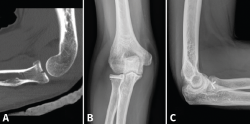

Se solicitarán radiografías simples (Rx) anteroposterior (AP) y lateral. También pueden ayudar las proyecciones oblicuas. En fracturas de la cabeza del radio no desplazadas podemos ver un signo indirecto de hemartros en el perfil estricto, la distensión de las almohadillas grasas anterior y posterior o “signo de la vela” (Figura 1). En casos de inestabilidad asociada podremos ver subluxación de la cabeza del radio respecto al cóndilo humeral. Si hay sospecha de lesión de la membrana interósea solicitaremos Rx posteroanteriores (PA) de ambas muñecas (en posición neutra) y podremos ver variaciones a nivel cubital distal.

Figura 1. Signo de la vela: distensión de las almohadillas grasas anterior y posterior por el hemartros.